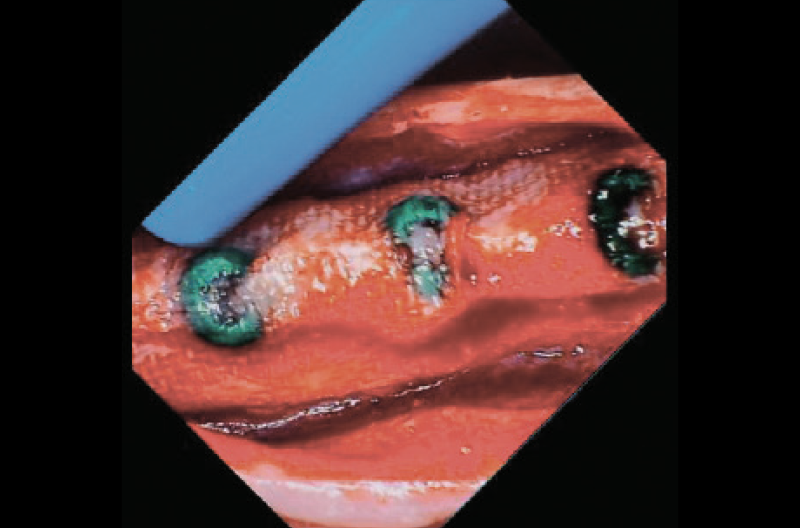

Preparati i siti con le frese di osseodensificazione dedicate, sono stati inseriti 4 impianti Leone Narrow XCN® 2.9 secondo le modalità sopra descritte. Solo per ridurre al minimo il rischio di riassorbimento osseo, soprattutto in cresta, zona maggiormente stressata nelle fasi di osseodensificazione ed espansione con le frese, ho preferito proteggere il sito chirurgico attraverso un minimo riempimento con biomateriali eterologhi e una membrana riassorbibile fissata attraverso chiodini di osteosintesi (Figg. 5 a, b).

Figg. 5 a, b – Radiografia endorale effettuata alla fine dell’intervento che evidenzia la posizione degli impianti Leone XCN® 2.9 e la presenza dei chiodini di stabilizzazione della membrana riassorbibile

Figg. 7 a-e – Fotografie endorali effettuate al momento della riapertura degli impianti Leone XCN® 2.9, trascorsi 5 mesi dall’intervento, che evidenziano la completa osteointegrazione degli impianti completamente sommersi e senza alcuna esposizione

Fig. 7 b

Fig. 7 c

Fig. 7 d

Fig. 7 e